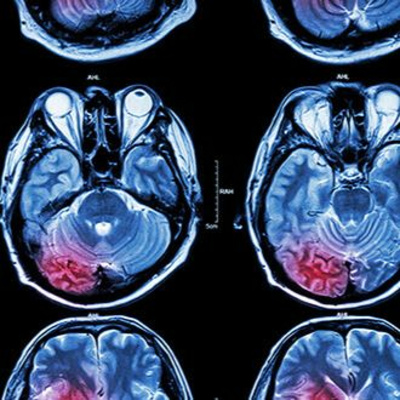

Artikel lesen: https://hnf.link/jip1 Kürzlich wurden neue Studienergebnisse veröffentlicht, die in einem Forschungsprojekt der St. George´s University of London in Zusammenarbeit mit der Dove Clinic gemacht wurden.